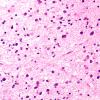

NEOPLASMS (GLIAL)

Astrocytoma, IDH-mutant, WHO Grade 2 (5)